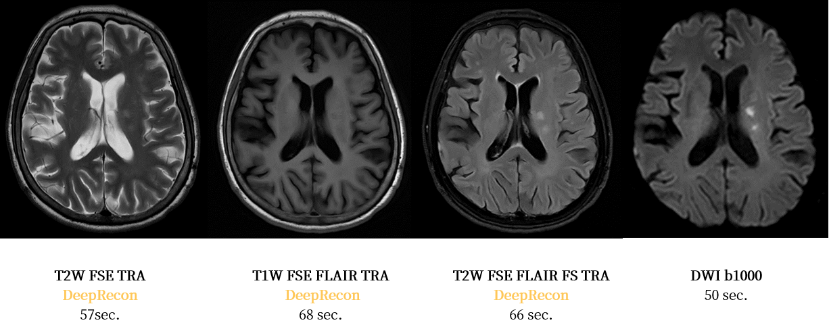

新进驻的uMR 780 3.0T 磁共振,凭借突破性技术优势,成为高原病诊断的 “超级雷达”:其搭载的 DeepRecon® 智能深度重建技术,在神经影像领域掀起效率与精度的双重革命 —— 仅需约 4 分钟即可完成头颅神经扫描,大幅提升高原地区检查效率。

同时能有效抑制图像噪声,在严苛环境下清晰呈现细微解剖结构,让高原脑水肿、脑血管病变等早期病灶无所遁形,为脑卒中患者抢出黄金救治时间。

DeepRecon®技术助力高原脑血管疾病精准成像